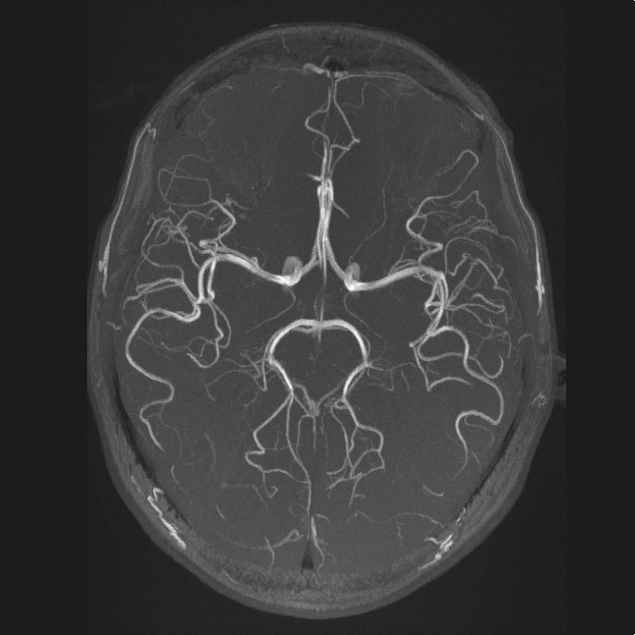

МРТ венография: Изображения сосудов головного мозга